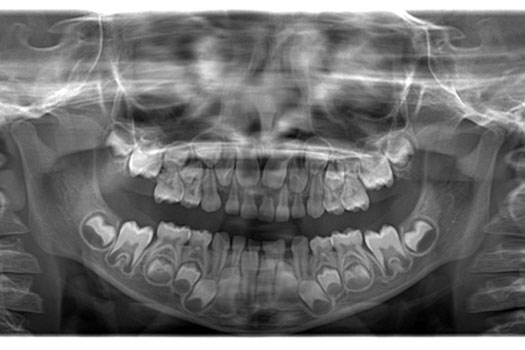

PANORÁMICA PEDIÁTRICA

Da una vista panorámica de todos los dientes, es un estudio que se realiza a los niños desde tempranas edades hasta los 12 años, se debe hacer de rutina para comenzar cualquier procedimiento en odontología pediátrica, permite visualizar la secuencia de erupción dental, hacer predicción de los espacios requeridos para los dientes definitivos y verificar la formula dentaria (exceso o falta de dientes). Así mismo este estudio permitirá ver patologías en los huesos maxilares, tamaño de raíces dentales, nivel de hueso en el que están soportados los dientes.